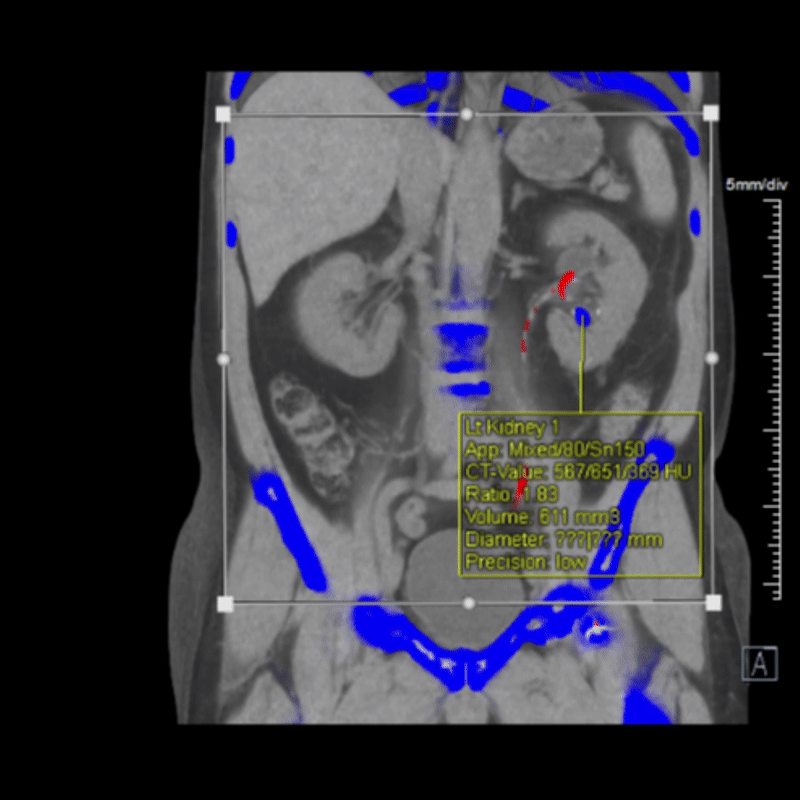

Dual energy CT offers a major improvement by allowing radiologists to identify stone composition non-invasively. By capturing images at two X-ray energy levels, it distinguishes uric acid from calcium and other stone types based on their material-specific attenuation patterns. This helps guide treatment from the start, determining whether a patient may benefit from medical management or needs surgical intervention. It can also reduce the need for repeat imaging or exploratory procedures. For patients with recurrent stones, DECT provides valuable insight into stone behavior over time, supporting more personalized prevention strategies.

Figure D: Axial dual energy CT images of the abdomen, used for analyzing the composition of kidney stones.

Figure E: The axial images of the abdomen from Figure D, now processed to analyze the composition of the kidney stone (indicated by the arrow).

Figure F: Processed images from Figure E, showing graphics that detail the stone’s size, volume, and composition.